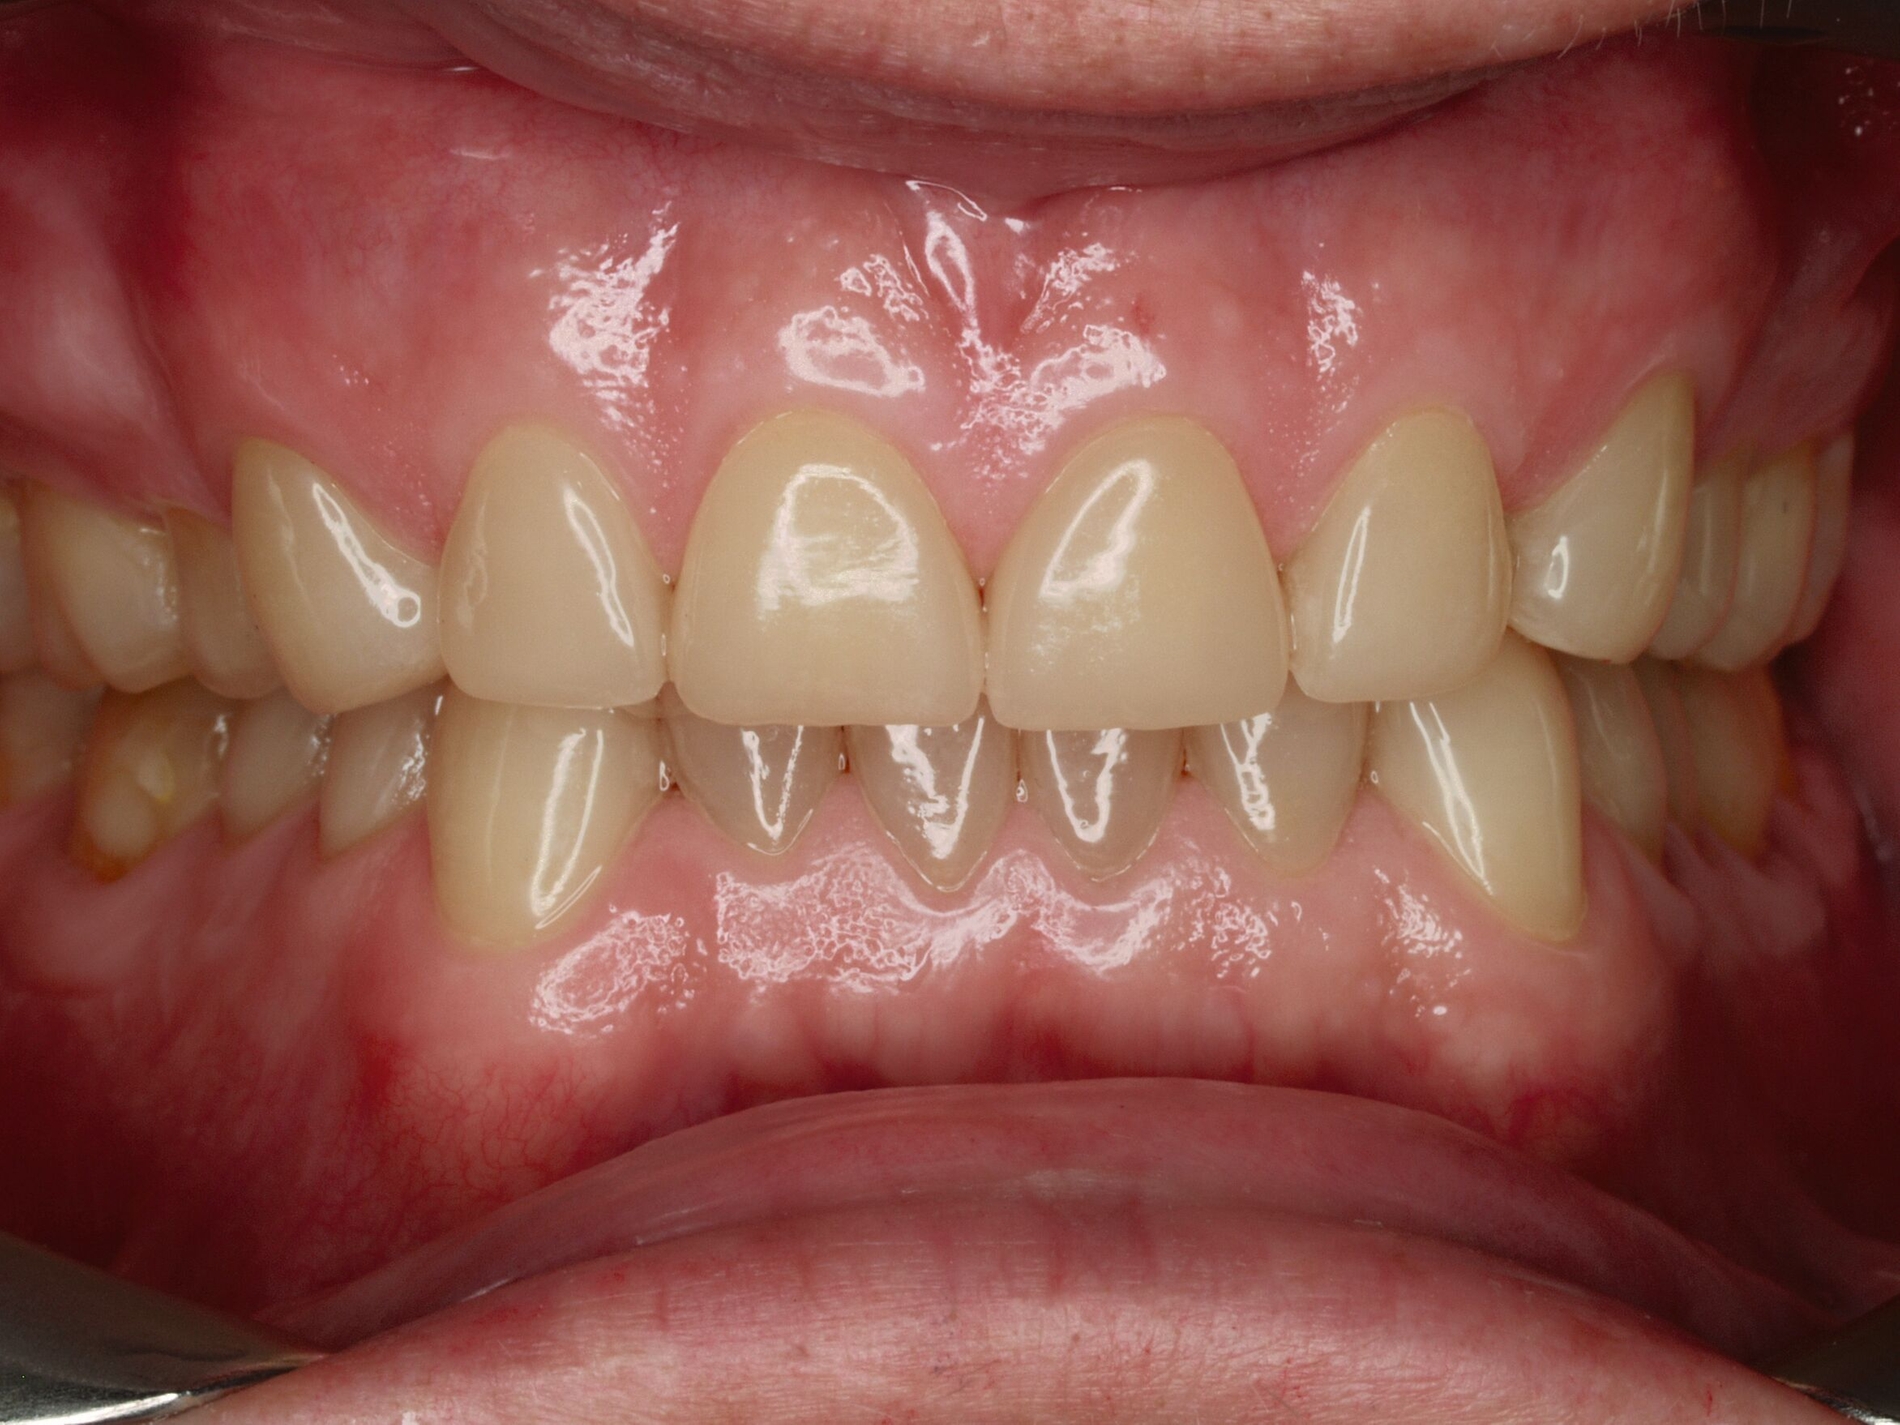

Das unter Beteiligung des Autors entwickelte Tooth Wear Evaluation System (TWES) 2.0 [Wetselaar et al., 2020] identifiziert per Screening Patienten mit erhöhten Verschleißwerten, vergleichbar mit dem PSI in der Parodontologie oder dem CMD-Kurzbefund. Bei auffälligen Werten folgt ein differenzierter Zahnverschleiß-Status einschließlich der Erfassung oraler und vestibulärer Substanzverluste [Wetselaar et al., 2016 sowie von Pathologie-Symptomen und einer strukturierten Diagnose [Tonetti und Sanz, 2019; Wetselaar, 2020]. Den Einsatz in der Praxis illustriert der in den Abbildungen beschriebene Patientenfall aus dem CMD-Centrum Hamburg-Eppendorf.

Im Beispiel ist daher die Diagnose ein generalisierter erheblicher und lokalisierter moderater pathologischer Zahnverschleiß überwiegend mechanischer und zudem chemischer Ursache. Die sich daraus ableitende Erkenntnis ist, dass in allen Sextanten Zähne freiliegende Dentinkerne aufweisen (generalisierter moderater Zahnverschleiß), dass darüber hinaus Zähne erheblich geschädigt und somit gefährdet sind, dass Merkmale eines pathologischen Geschehens bestehen – und dass als Ursache neben dem dominierenden Bruxismus ein Säureeinfluss hinzukommt.

Auch wenn Restaurationen nach Möglichkeit vermieden werden sollten, ist deren Verfügbarkeit für die Betroffenen individuell höchst wichtig, weil sie bestehende Schmerzen beseitigt, die verlorengegangene Kauleistung wiederherstellt und ästhetische und nicht zuletzt auch phonetische Einschränkungen aufhebt. Bei dem in den Abbildungen beschriebenen Fall korrelierte der erhebliche Zahnverschleiß mit der Lokalisation der Zahnschmerzen des Patienten. Direkte Restaurationen mit Kompositen hatten keinen Bestand. Die durchgeführte restaurative Behandlung hingegen hat Bestand, die Schmerzen waren danach umgehend verschwunden und sind seit zehn Jahren nicht wiedergekehrt.

Dabei führt die Verfügbarkeit hochfester Dentalkeramiken heute zu viel weniger invasiven Restaurationen als früher durchgängig übliche metallkeramische Kronen, und die Transluzenz der keramischen Werkstoffe ermöglicht zudem natürlichere Restaurationen. Der beschriebene Behandlungsfall zeigt, wie eine mehrstufige Zahnverschleiß-Diagnostik im Praxisalltag umgesetzt wird, mit initialem Zahnverschleiß-Screening und einer im Bedarfsfall erfolgenden erweiterten Diagnostik per Zahnverschleiß-Status.